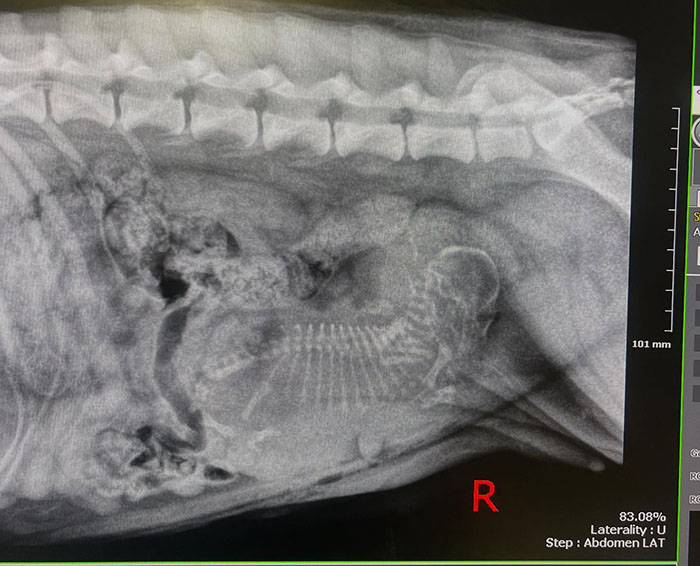

This came as a shock to everyone involved because no one had even the slightest suspicion that Salem might’ve been pregnant. And when everyone finally got their bearings, the X-ray that the vet performed brought a second, arguably even bigger surprise.

“Salem was pregnant with ONE giant puppy,” Christina said, explaining that this is called a singleton puppy and it’s a very unusual occurrence for dogs. “The puppy was literally taking up her whole uterus!”